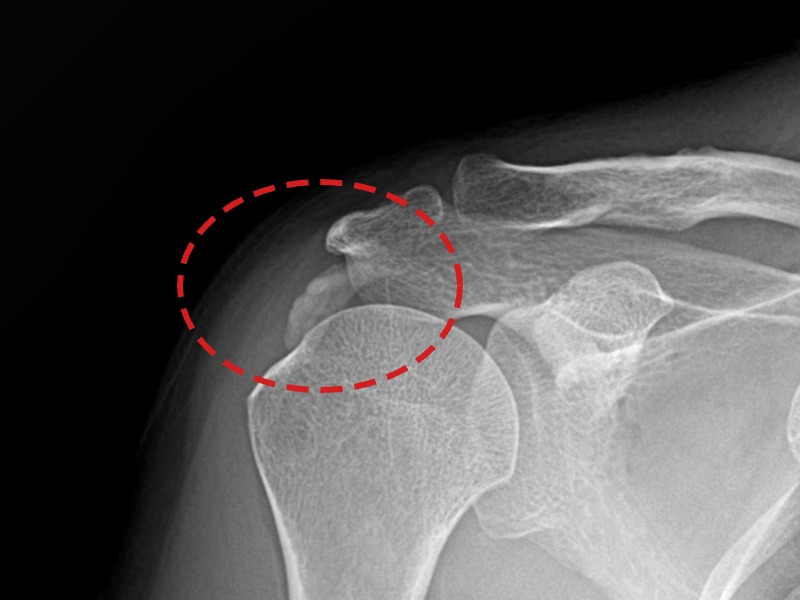

[촬영시기:21.11.04~21.11.09]

[석회분쇄흡입술] 우측 어깨 극심한 야간 통증으로 수면이 불가능해진 50대 여성 환자로, X-ray에서 우측 극상근건 내 석회 침착이 확인되어 석회분쇄흡입술을 시행하였습니다.